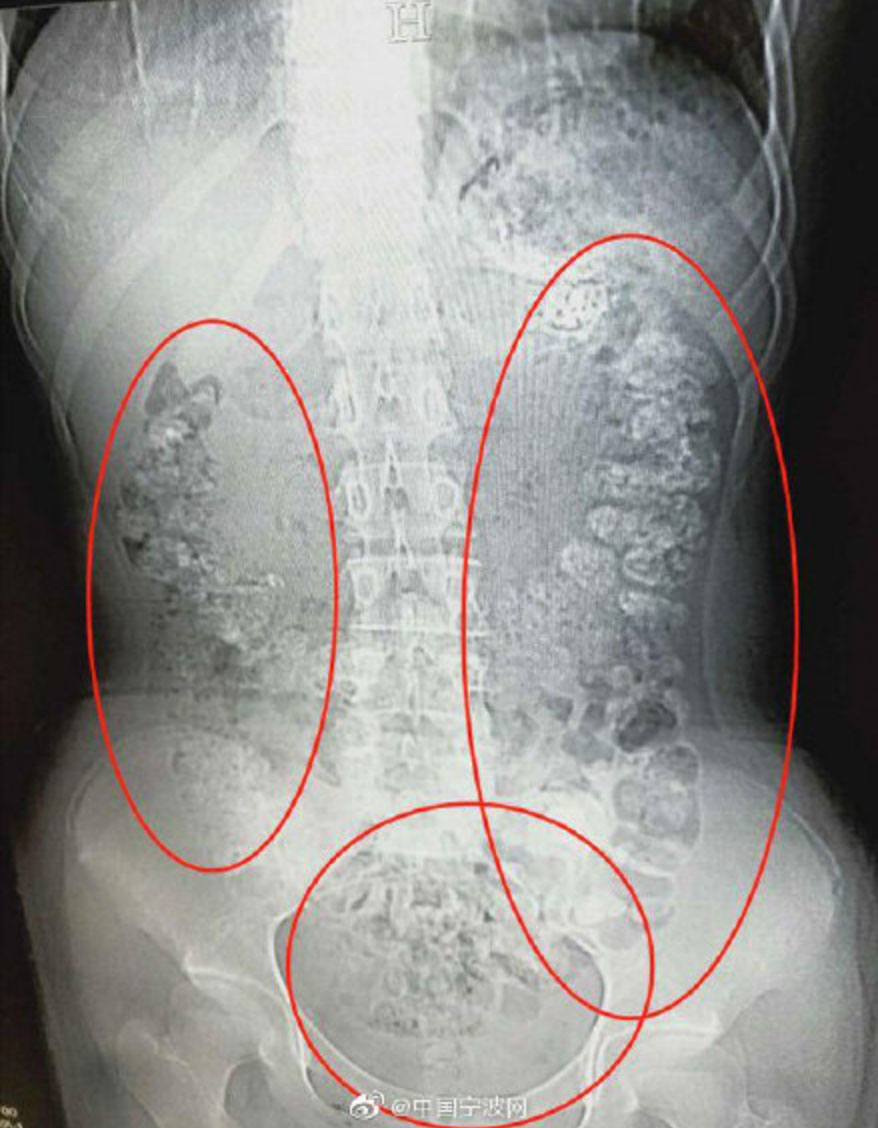

According to AsiaOne, a 14-year-old girl from Zhejiang province told her parents that she had stomach pain, wasn’t hungry, and hadn’t had a bowel movement in at least five days. She was examined at a local hospital, and after the docs couldn’t immediately determine what was wrong, they ordered a CT scan of her abdomen. When Dr. Zhang Louzhen reviewed the images, he saw more than one hundred “granular shadows” in her abdomen, scattered from her stomach to… well, let’s just call it the far end of her alimentary canal.

The doctor asked what she had eaten before her symptoms started, and she said that she’d had a bubble tea five days ago. A single bubble tea. To that, Dr. Zhang is said to have blinked and asked her again: Seriously, what you have been eating? She stuck to her story, but the doc said she was probably just afraid of telling her parents how much boba she’d been downing. “So many undigested ‘pearls’ are not accumulated [from] a cup of milk tea,” he told The Paper. “ It would be caused by drinking [it] for a while.”